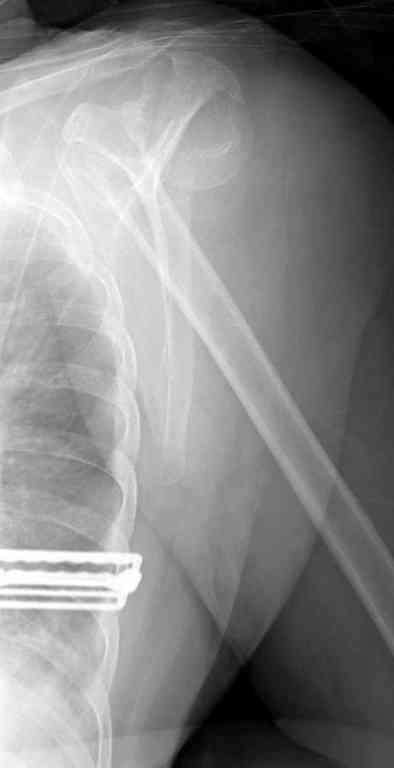

По Neer операцию рекомендовали только тогда, когда угол между диафизом и головкой составляет около 45 градусов, и переломы с меньшим углом смещения считали благоприятным для функционального результата.

Хотя "варусная импакция" в проксимальном отделе плеча срастается хорошо консервативными мерами, но в результате при восстановлении такие больные теряют часть отведения, и тем более у больной варус осложнен еще сгибанием.

Закрытые репозиции без фиксации из-за вторичного смещения неэффективны, поэтому рекомендуется репозиция с фиксацией. Методик много, кто чем владеет и отдает предпочтение закрытые-открытые, перкутанные, с блокирующими пластинами, гвоздь, множественными спицами или методом спиц по Лазареву, и осторожно с манипуляциями из=за возможности повреждения аксиллярного нерва - частый вид осложнении.